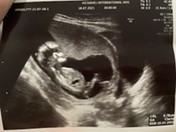

อันนี้ตอน21 wค่ะ ตอนนี้23wแล้ว😊